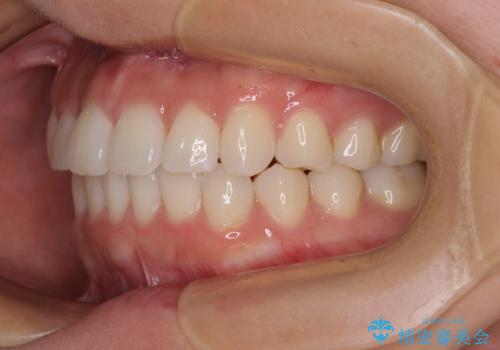

上下前歯のデコボコ ワイヤー装置で楽して改善

- 上下前歯のデコボコを気にして来院された患者様です。

ワイヤー矯正でもインビザラインでも、どの装置でも対応可能でしたが、安価で楽して素早く治療を終えたいとのことで、メタルブラケット装置による矯正治療を行うこととしました。

治療中は大きなトラブルもなく、予定の1年半でスムーズに治療を終えることができました。